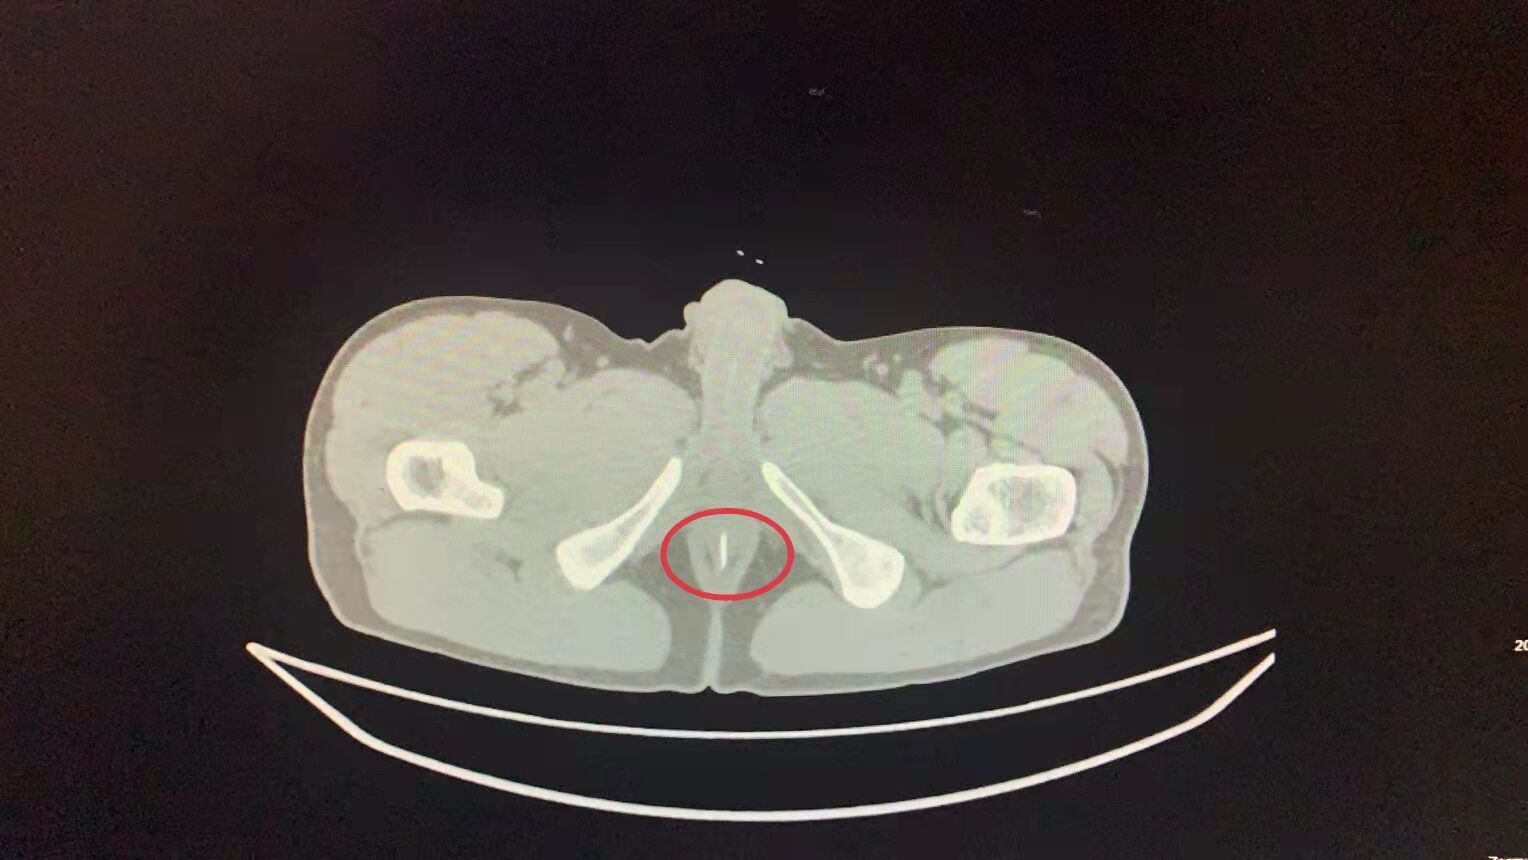

CT影像显示樊先生肛门处有异物(红圈处)。

3月8日下午,49岁的樊先生突然感觉肛门刺痛,摸起来有个小包。没有痔疮病史的樊先生有点纳闷,但并未引起重视。当天晚上,樊先生感觉疼痛越来越剧烈,这才赶紧到医院就诊。该院胃肠外科医生接诊后,为樊先生进行了详细检查。据接诊的宋亚锋医生介绍,CT影像显示樊先生肛门处有一处低密度影,但是暂不能判断是什么东西。此时樊先生患处已经发炎,形成一处脓肿,需要及时处理。医生立即为樊先生进行了急诊手术,取出了异物。